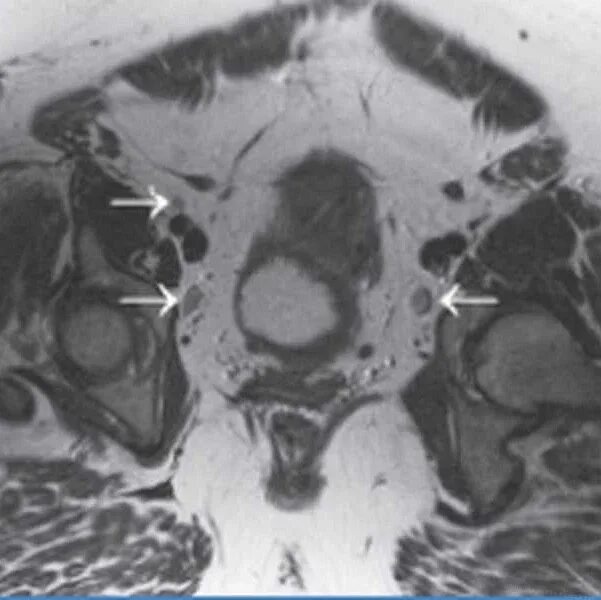

Метастазы в паховых лимфоузлах